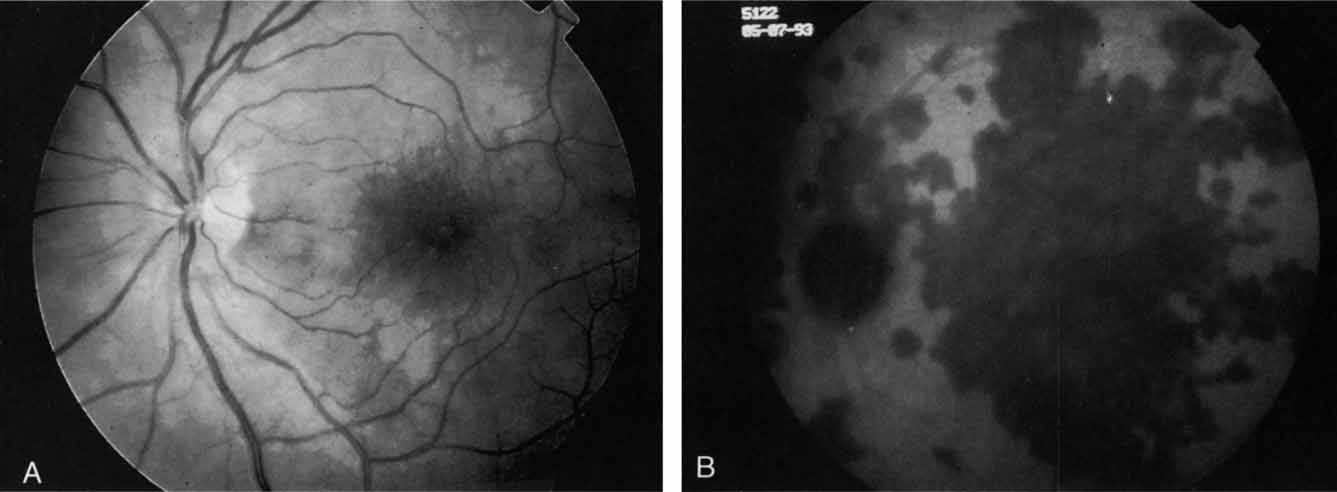

Most promising in this category of inflammatory choroidopathies is a better detection and understanding of the lesions of multifocal choroiditis. Multiple large, scattered, hypofluorescent spots are seen on ICG angiography, particularly in the later phases of the angiogram69 (Fig. 18). These lesions are not evident either on clinical examination or on fluorescein angiography. In addition to having these larger hypofluorescent lesions, patients with multifocal choroiditis have smaller dot-like lesions and hyperfluorescent foci that do not correlate with lesions seen clinically or by FA. They involve the posterior pole and in some patients extend into the mid-periphery. There is also a “papillotropic” involvement, with confluent hypofluorescent lesions surrounding the optic nerve,69 which may be useful in understanding the associated blind-spot enlargement evident in this condition.70 Other zonal visual field defects have been associated with this condition,70 and corresponding ICG abnormalities have been documented in some patients.69

Fig. 18 A. Clinical photograph of a patient with active inflammation associated with multifocal choroiditis. An atrophic scar from previous laser photocoagulation treatment is noted in the temporal macula. The patient reported visual disturbance, and an enlarged blind spot was noted on visual field testing. B. Late-phase indocyanine green study demonstrating a multitude of hypofluorescent spots that were larger than those seen with multiple evanescent white dot syndrome and more numerous and more extensively distributed than appreciated on clinical examination. Note that there is marked confluence of these lesions around the optic nerve, which may help to explain the enlarged blind spot noted on visual field testing.

Natural history data indicate that with progressive increase in vitritis and associated choroidal inflammation, an increase in the number and extent of these hypofluorescent lesions can be documented.40 Furthermore, use of oral steroid therapy as a means of controlling this inflammatory process has been documented to produce not only clinical resolution of the inflammatory process but also corresponding resolution of the hypofluorescent lesions seen on ICG angiography.69 These clearly demonstrated lesions not only may lead to a better understanding of the process of inflammation involved in multifocal choroiditis and potential management strategies but also may serve to differentiate this condition from the ocular histoplasmosis syndrome.

In contrast to multifocal choroiditis, ocular histoplasmosis syndrome does not demonstrate any large, hypofluorescent lesions on the ICG angiographic examination.69 Instead, there are frequently mid- and late-phase hyperfluorescent lesions in the posterior pole in areas that appear normal both clinically and on fluorescein angiography (Fig. 19). These hyperfluorescent lesions may represent sites of subclinical choroidal inflammation. The presence of these lesions on ICG angiography not only may serve to distinguish the histoplasmosis syndrome but also may serve to explain the apparent de novo appearance of new atrophic spots and CNV in what was previously presumed to be normal chorioretinal tissue.

Fig. 19 A. Clinical photograph of a patient with recurrent choroidal neovascularization associated with ocular histoplasmosis syndrome. A few focal “histo spots” are noted in the superior macula. B. Late-phase indocyanine green study demonstrating hyperfluorescence in the central macula corresponding to recurrent neovascularization. Multiple intensely hyperfluorescent dots are noted throughout the macular region, which do not correspond to any detectable lesion noted clinically or via fluorescein angiography. These focal spots may represent sites of subclinical inflammation at the level of the choroid.